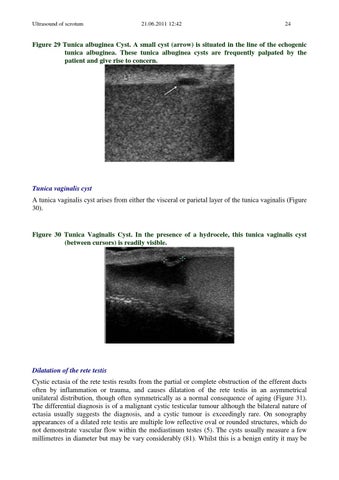

Figure 29 Tunica albuginea Cyst. A small cyst (arrow) is situated in the line of the echogenic tunica albuginea. These tunica albuginea cysts are frequently palpated by the patient and give rise to concern.